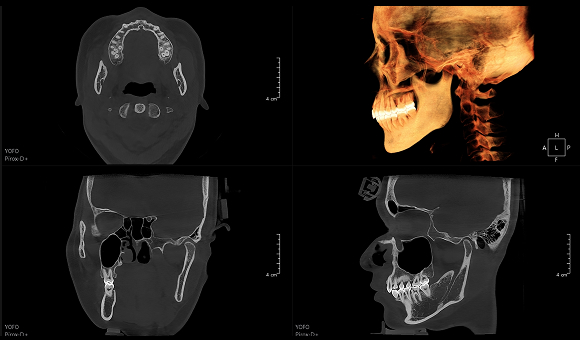

只需一次单圈扫描即可获得CT、3D全景和3D正/侧位影像,并能同时生成3D TMJ视图

提高诊疗效率,避免过度检查,减少患者所受的辐射

• CT

CT

• 3D全景

3D全景

• 3D 正侧位

3D 正侧位

• 3D TMJ视图

3D TMJ视图